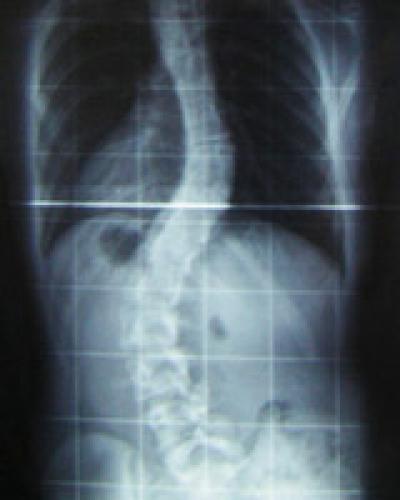

Physicians have recognized scoliosis, the abnormal curvature of the spine, since the time of Hippocrates, but its causes have remained a mystery -- until now. For the first time, researchers have discovered a gene that underlies the condition, which affects about 3 percent of all children.

Severe scoliosis is typically treated by surgery or by wearing an orthopedic brace, which straightens the curvature over time. Most minor spinal curves can be monitored by a doctor and do not progress to the point where treatment is necessary.